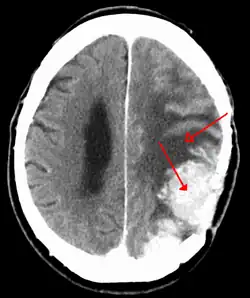

A meningioma that previously had been operated on, with surrounding edema

Meningiomas are visualized readily with contrast CT, MRI with gadolinium,[23] and arteriography, all attributed to the fact that meningiomas are extra-axial and vascularized. CSF protein levels are usually found to be elevated when lumbar puncture is used to obtain spinal fluid. On T1-weighted contrast-enhanced MRI, they may show a typical dural tail sign absent in some rare forms of meningiomas.[18]